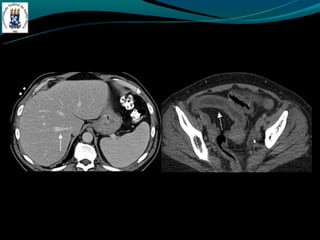

GÁS NO SISTEMA PORTA

-Mais frequentemente associado:

-Isquemia intestinal nos adultos

-Enterocolite necrosante nos RN

-Outras causas: colonoscopia recente, sonda de gastrostomia, DII,

diveticulite, abscesso abdominal…

GÁS NO SISTEMAPORTA -Mais frequentemente associado: -Isquemia intestinal nos adultos -Enterocolite necrosante nos RN -Outras causas: colonoscopia recente, sonda de gastrostomia, DII, diveticulite, abscesso abdominal…